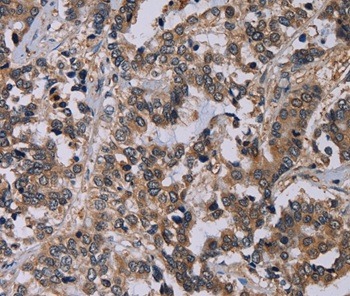

Immunohistochemical analysis of paraffin-embedded Human liver cancer tissue using #36647 at dilution 1/60.

Immunohistochemistry: 1:100-1:300